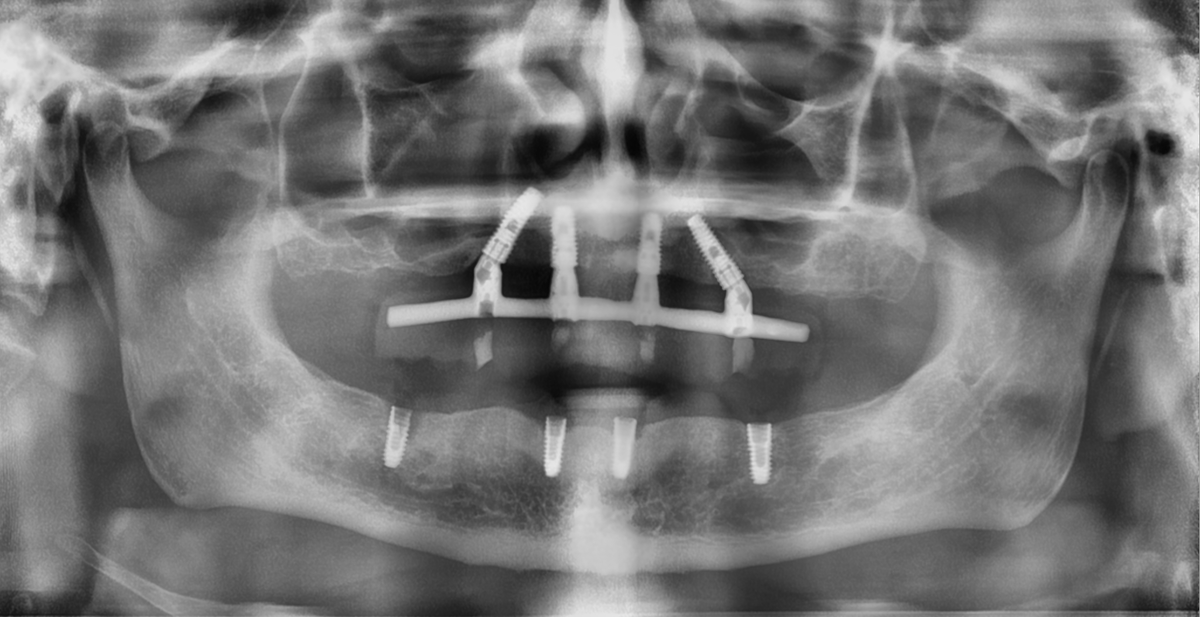

Снимок на моей первичной консультации ( лопнувший имплант 45, 42,32 - оголение на 20%)

И контрольный рентген снимок после финального протезирования ~ через 8 месяцев (все имплантаты в костной ткани, стабильны):

"всё на 5-ти"